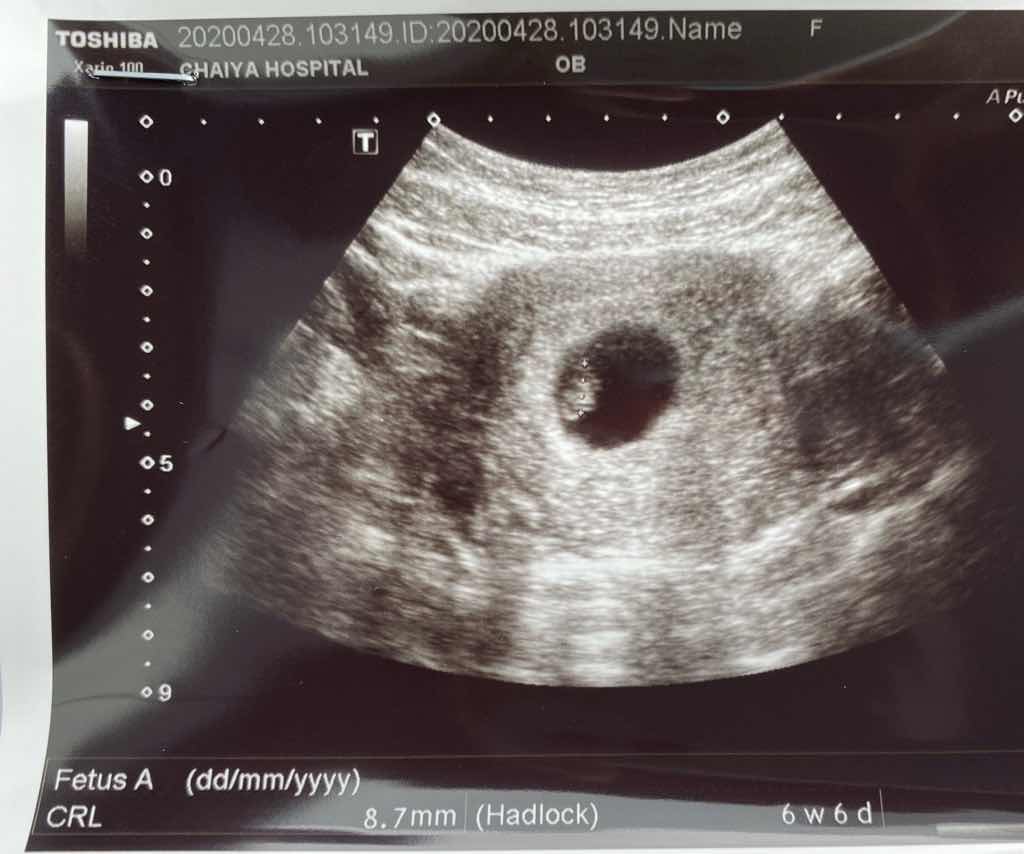

ซาวด์เมื่อวานค่ะ 6w6d